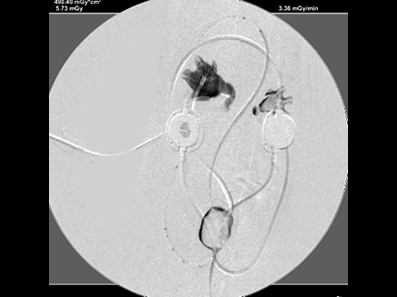

造影で漏れがないか何度も確認

必ず透視下にて漏れがないか何度も確認をします。 透視をしないとシステムや装着部分からの漏れが確認されたり、トラブルが考えられます。

実際、他院で装着して漏れがあるなどの相談をうけることがしばしばあります。

透視下にて実施すれば適切な位置に装着できます。

綺麗につければ感染や漏れもほとんどなく、経過はとても良好です。

透視下にて腎盂に入っていることを確認。

ここにカテーテルを装着していきます。